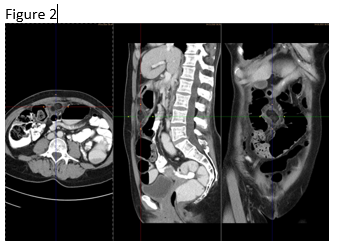

Figure 2: Computed tomography confirmed the finding of a partially infarcted omentum.